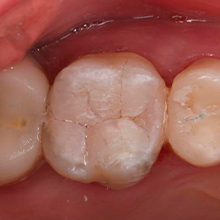

Restauração com Resina Provisória Pos Selamento